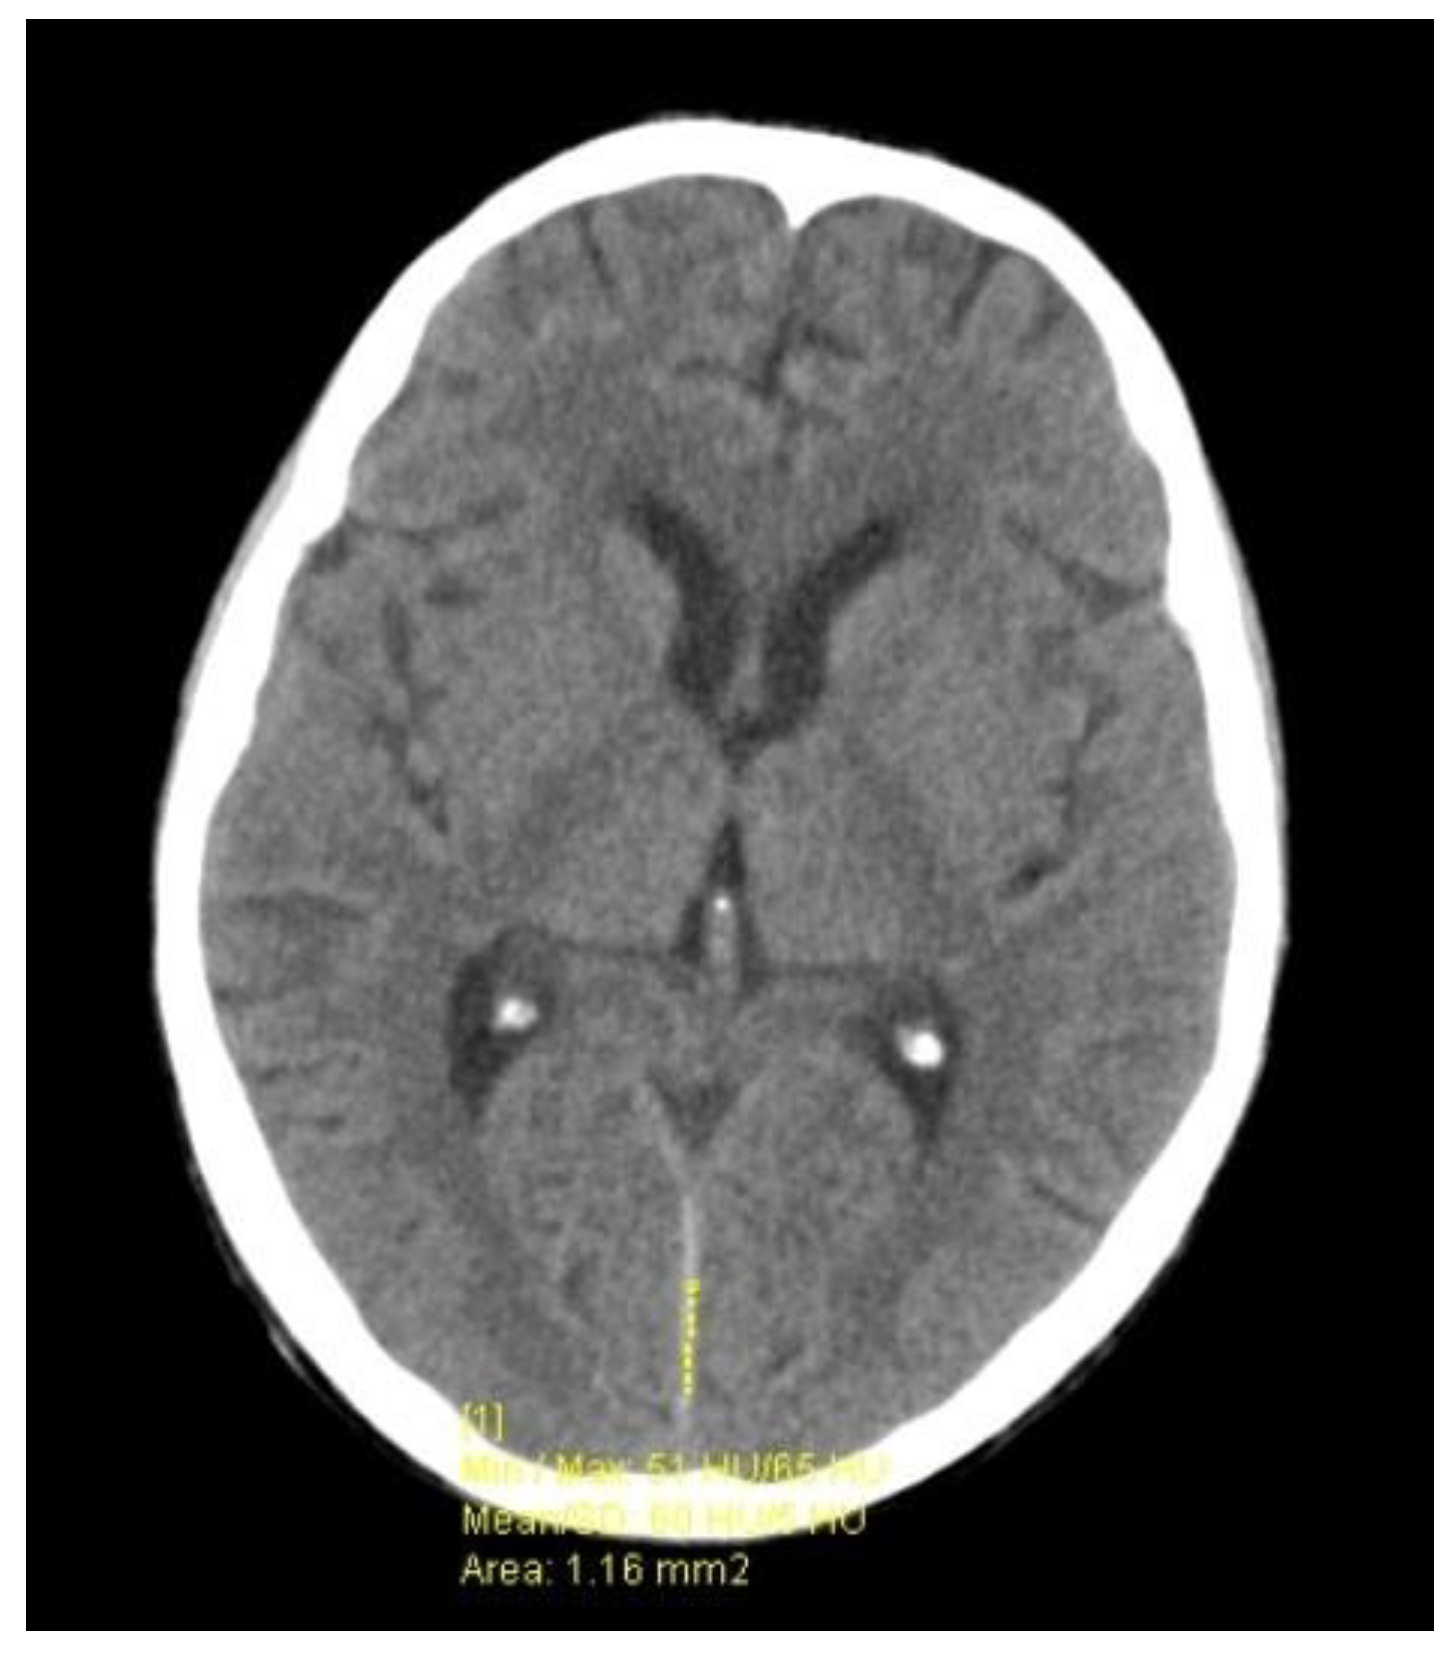

2. Case Presentation